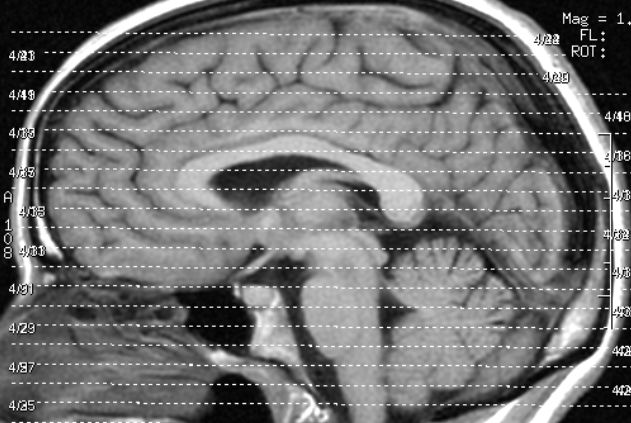

Mittels Elektroenzephalographie – kurz EEG – werden die Hirnsignale über die von ihnen erzeugte elektrische Spannung auf der Kopfhaut gemessen. Eine Software wandelt das Ganze in entsprechende Befehle um. Die Forscher machen aus den Hirnsignalen akustische Signale – das erleichtert die Auswertung. Dazu haben sie eigens einen Audioraum mit 40 Lautsprechern in den Wänden eingerichtet.